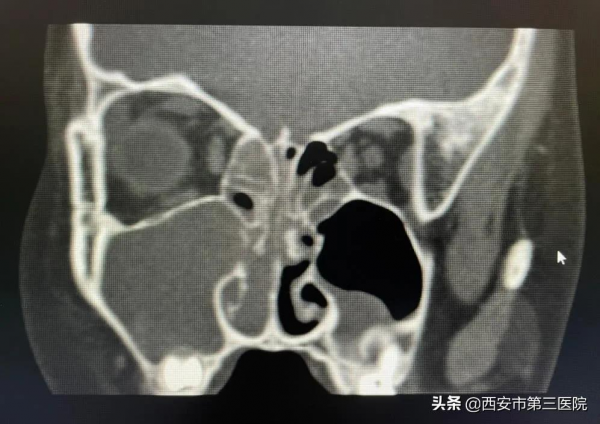

進一步檢查,CT進一步驗證了王主任的診斷,萱萱的確患有鼻息肉,而且是出血性鼻息肉,同時患有右側鼻竇炎。